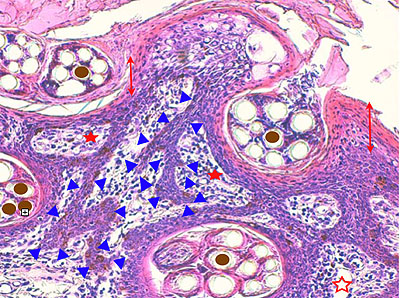

Photo 6 (Hémalun Eosine X 400) : vue rapprochée au fort grossissement d’une crête épithéliale

émanant de la gaine épithéliale externe d’un follicule pileux (portion infundibulaire).

L’aspect filiforme et longiligne s’accompagne d’une certaine perte de polarité des cellules basales

dont le grand axe cytoplasmique devient parallèle au grand axe de la crête épithéliale, au lieu

d’être perpendiculaire. La couche la plus basale perd ainsi son habituel aspect palissadique.

Légendes de la Photo 6 :

- Triangles bleus clairs : contours de crêtes épithéliales allongées, filiformes, ramifiées et branchues, peuplées de cellules basales hyperbasophiles, émanant de la gaine épithéliale externe des infundibula folliculaires

- Flèches rouge : parakératose folliculaire

- Étoiles rouge pleines : Le derme est faiblement à modérément inflammatoire (infiltrat mononucléé)

- Étoiles rouges claires : angiectasie des capillaires sanguins

- Ronds marron :tiges pilaires

- Flèches orange : mélanocytes

- Flèches jaune : mélanophages